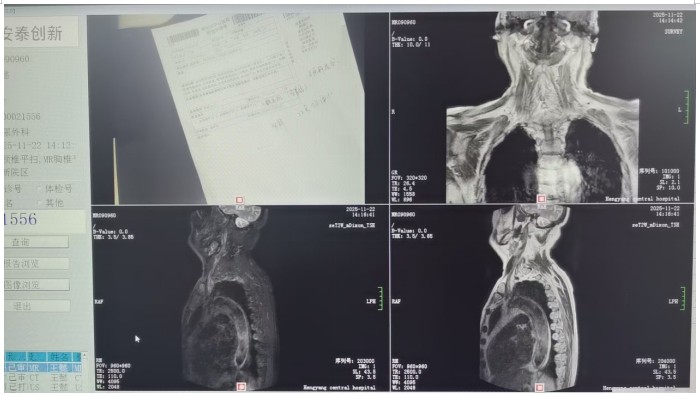

馬子芳團(tuán)隊(duì)詳細(xì)詢問(wèn)患者病史和治療情況后,對(duì)患者進(jìn)行了相關(guān)輔助檢查,初步診斷患者為神經(jīng)源性膀胱??紤]到老人82歲高齡、基礎(chǔ)疾病多等情況,團(tuán)隊(duì)多次組織病例討論,與患者及家屬充分溝通,最終決定為患者實(shí)施微創(chuàng)、可逆的骶神經(jīng)刺激器植入術(shù)進(jìn)行治療。很快,馬子芳團(tuán)隊(duì)為老人實(shí)施了一期骶神經(jīng)調(diào)控電極植入術(shù),術(shù)中精準(zhǔn)定位,成功穿刺骶3神經(jīng)孔,術(shù)中測(cè)試各位點(diǎn)的運(yùn)動(dòng)應(yīng)答、感覺(jué)應(yīng)答明顯,無(wú)不良反應(yīng)。